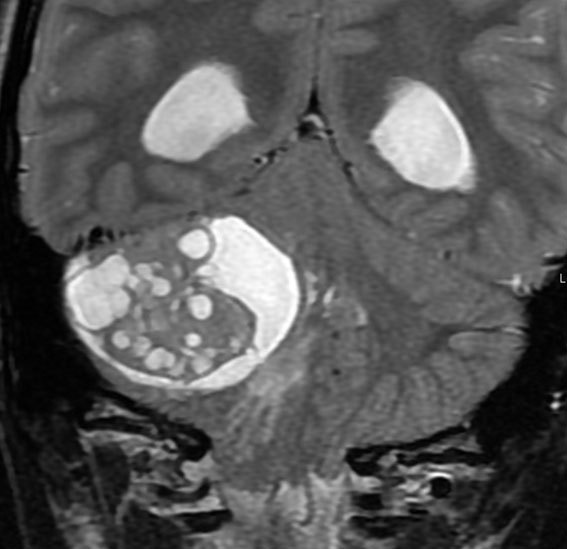

3歳発症の髄芽腫です。M2/M3でしたから,生検術などせずに,脳室ドレナージをして,ICE化学療法で治療を開始しました。

化学療法を開始して21日目のMRIです,腫瘍はかなり小さくなっています。この後に,手術摘出(病理確定)や脳脊髄照射などをしました。この例はいずれにしても化学療法をする必用があったものです。

2歳の子どもにできたmedulloblastoma with extensive nodullarityのMRI CISS image矢状断層。多数の結節に分かれるこのタイプの髄芽腫は3歳未満の小児に発生し,化学療法によく反応します(右は1コースのICE化学療法後の顕著な縮小を示します)。従って,classical medulloblastomaよりも予後が良いといえます。リスクを侵して全摘出する必要はなく,また幼児発生であることも考慮すれば放射線治療の intensityも高く設定する必要はないのかもしれません。同じ3歳未満のhigh-risk groupの髄芽腫といえども,2歳児のanaplastic medulloblastomaとは治療反応性に天地の開きがあります。